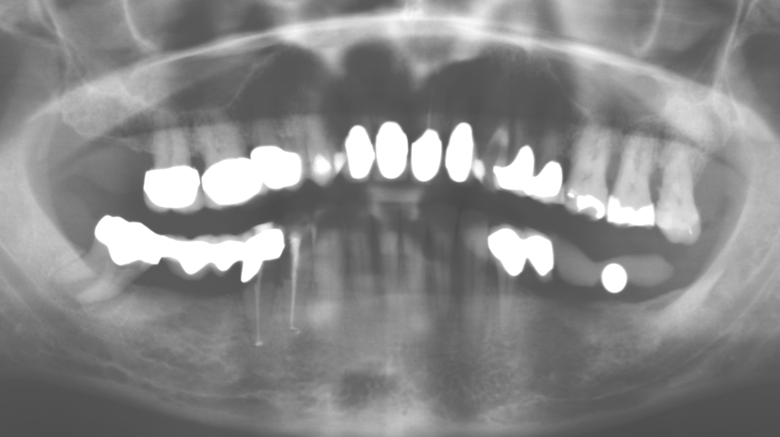

Für den klinischen Langzeiterfolg des parodontal kompromittierten Patienten ist die standardisierte und regelmäßige risikoadaptierte Betreuung im Rahmen der UPT der zentrale Baustein des Behandlungserfolgs. Dies gilt in besonderer Weise für Patienten, die nach erfolgreich abgeschlossener parodontaler Sanierung mit Implantaten versorgt wurden (Abb. 11a und b).